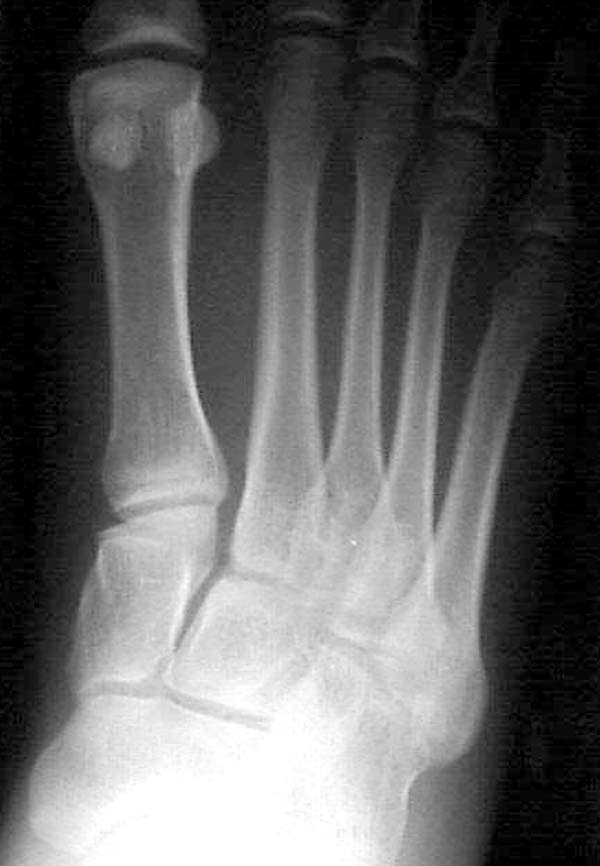

Имя     : Rt WB comparative.jpg

Тип     : image/jpeg

Размер  : 44245 байтов

Описание: отсутствует

Url     : http://weborto.net:8080/pipermail/ortho/attachments/20080320/e19da97a/attachment-0007.jpg